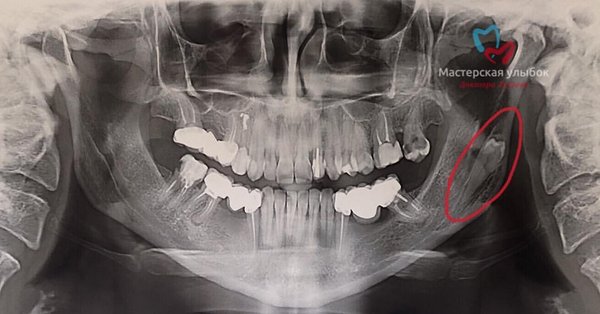

Ранее мы выставляли в историю пост, что не так на снимке а вот и ответ коварный зубик решил отдохнуть подальше от всех # как думаете какие дальнейшие действия будут?